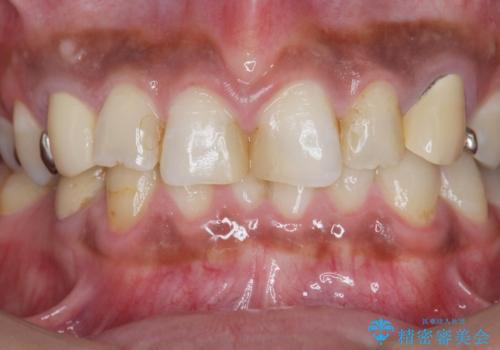

複数箇所コンポジット充填された前歯をセラミック治療

- コンポジットレジンの充填箇所がすり減ってしまい、形の悪くなった前歯の治療を希望され来院されました。

充填部位が大きく、再度充填をするには神経と近くなり抜髄のリスクが高まるため、劣化の少ないセラミックでフルカバーするセラミッククラウン治療を行うこととしました。

前歯の小さな虫歯は、除去したのちコンポジットレジンと言われる樹脂を充填する処置を行うことが多々あります。

しかし、経年劣化が早く着色や小さな虫歯が再発しやすいため、ある程度の大きさになってしまった場合セラミッククラウンで置き替えた方が神経を温存し長期的な予後の期待できる治療となります。